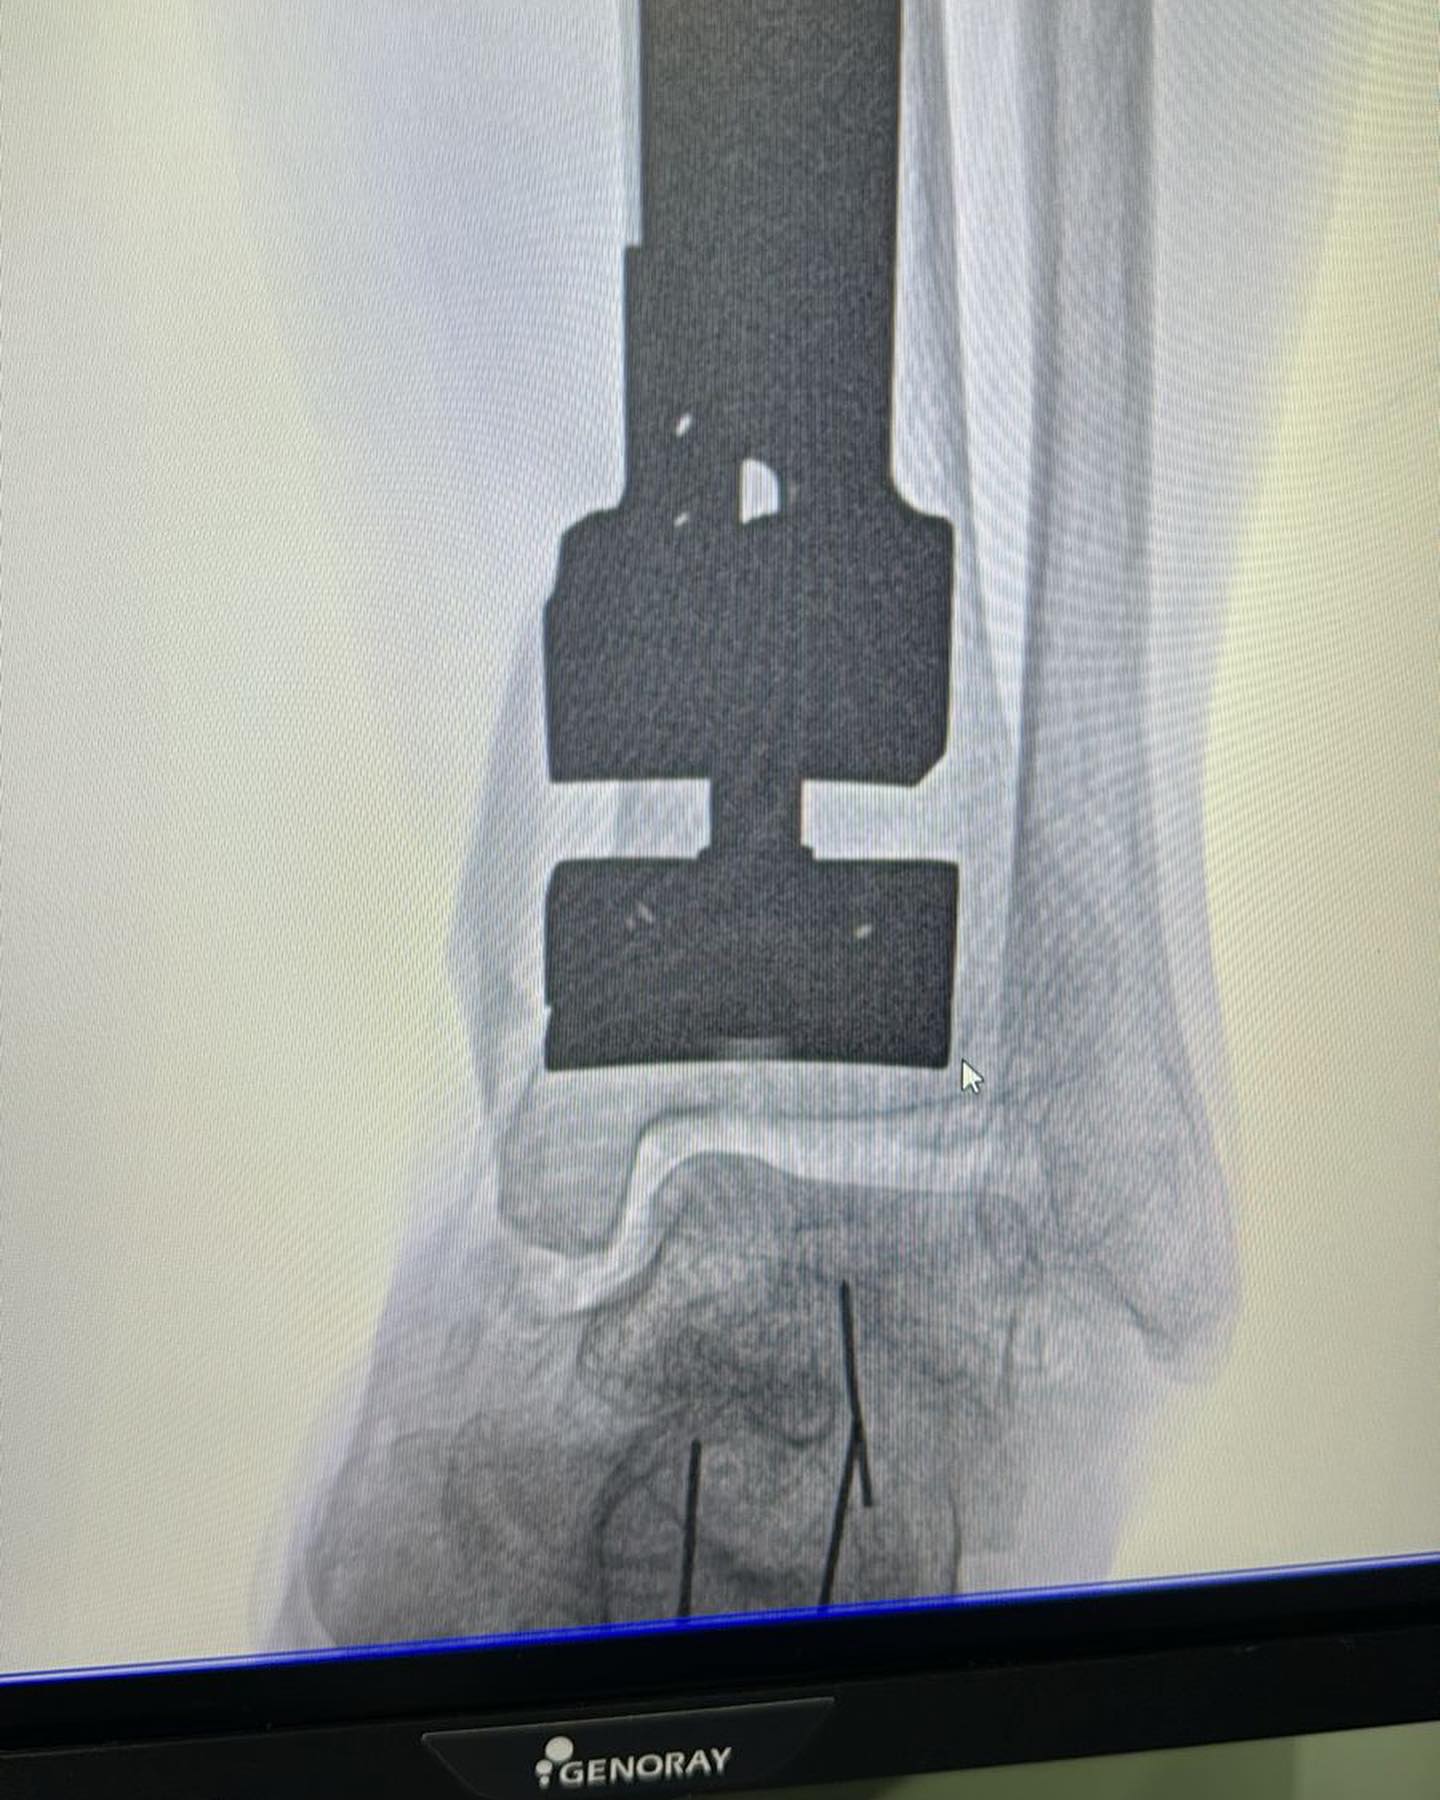

Este procedimiento quirúrgico consiste en sustituir la articulación dañada por una prótesis compuesta de metal y plástico, diseñada para restaurar la movilidad y aliviar el dolor.